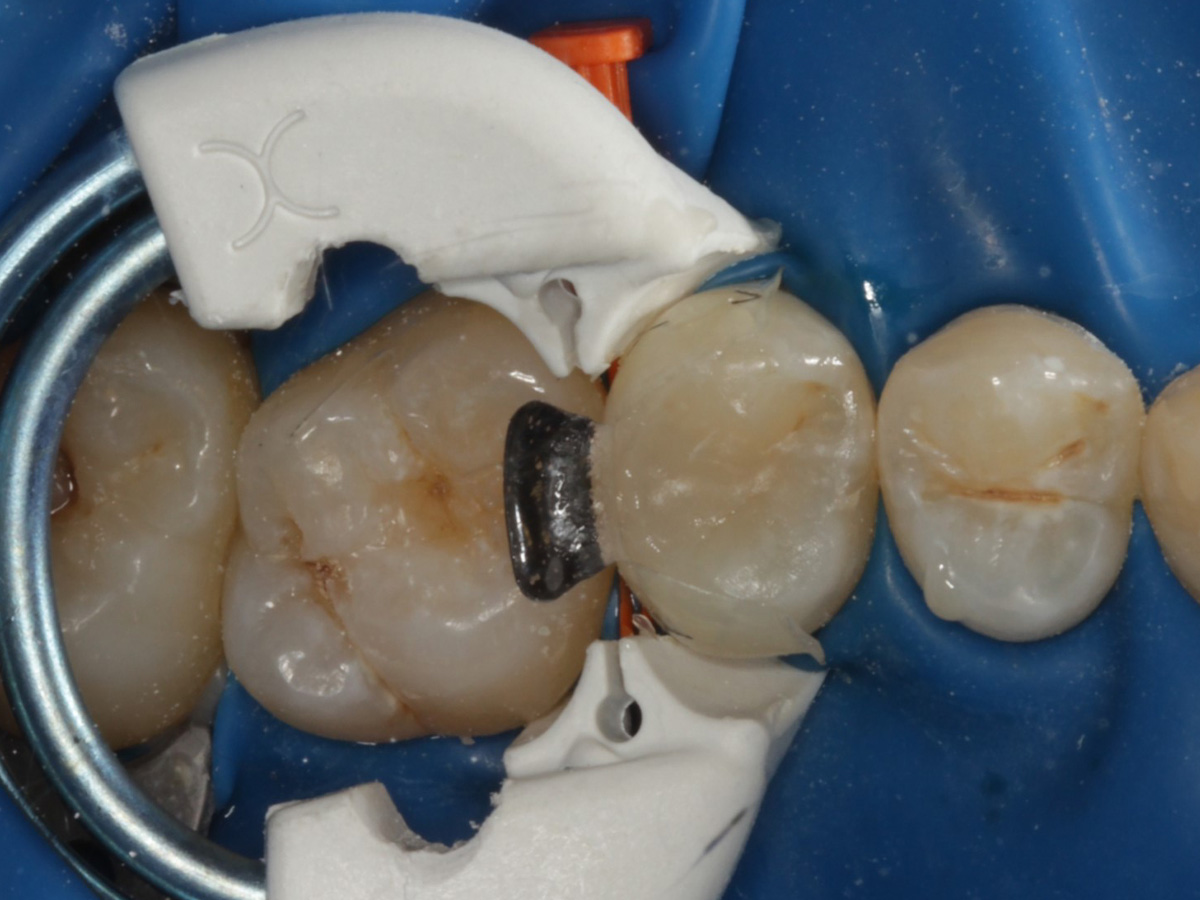

Abbildung 9

Height Indicator vor Auswahl der passenden Evolve Matrize

Abbildung 10

Nach Applikation der Matrize: Evolve Schwarz Prämolar- 7 mm; Schmelzätzung